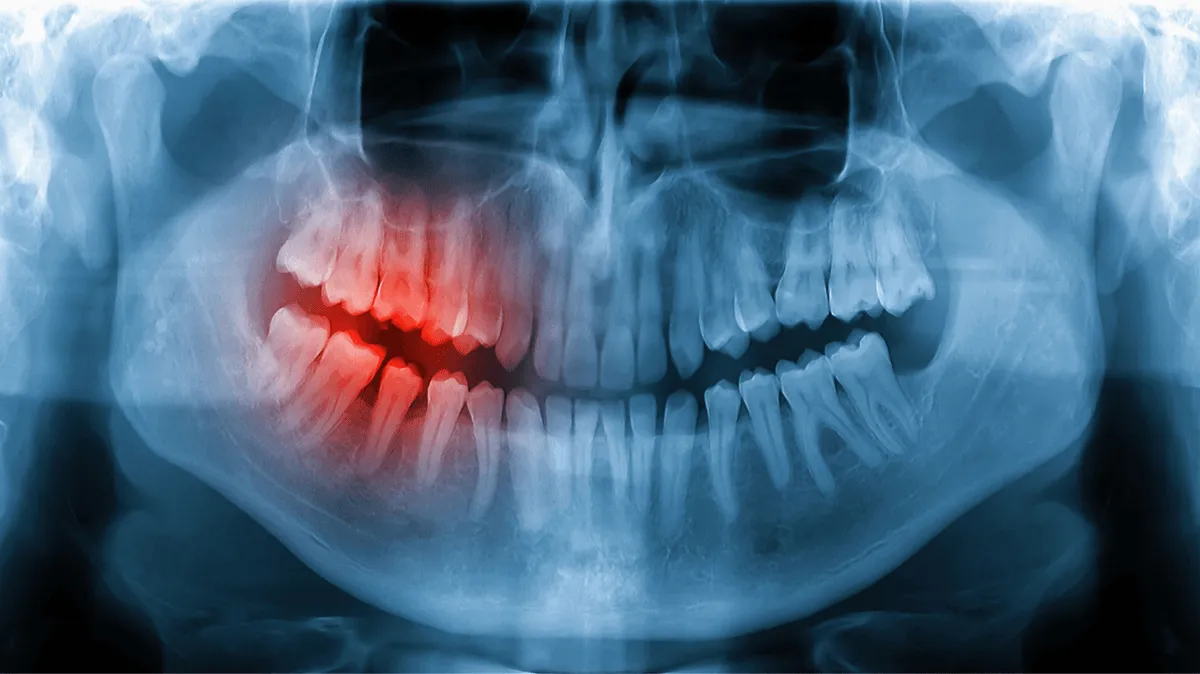

Перед процедурою лікар оцінює ситуацію на знімку, пояснює обсяг втручання та можливі варіанти. Ви розумієте, що саме будемо робити і чому.

Оглядаємо зуб і робимо знімок, щоб точно визначити обсяг втручання та уникнути ускладнень.